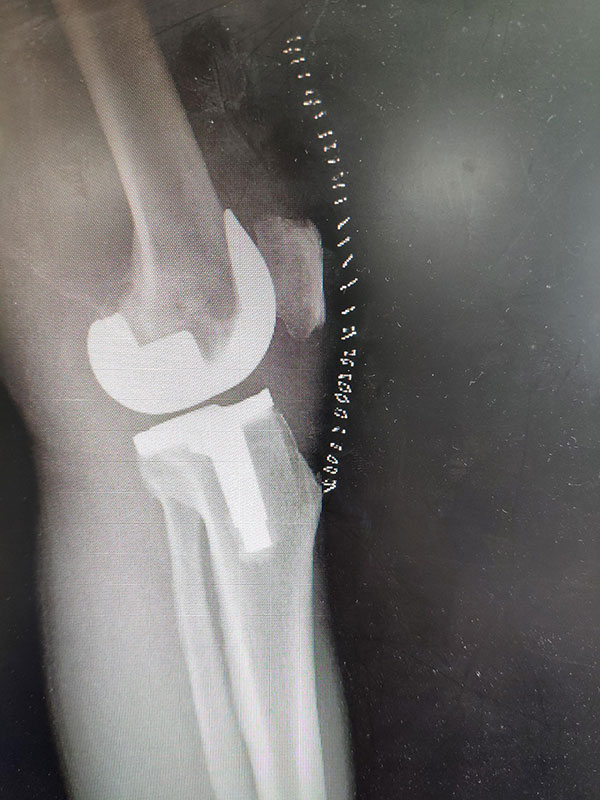

眾所周知,膝關節(jié)炎是中老年人的高發(fā)病,60歲以上患病率高達50%以上,75歲以上患病率高達80%以上,致殘率高達53%。中、晚期的骨關節(jié)炎幾乎沒有有效的控制辦法。近段時間在我科收治的骨關節(jié)炎患者中,有一位老年女性患者,73歲,身體極度消瘦,雙膝關節(jié)活動受限,嚴重畸形,疼痛劇烈,曾給予口服、外敷藥物治療,應用無效后前來我院就診。多年的膝關節(jié)疼痛讓老人苦不堪言,生活質(zhì)量大大下降。患者入院后,賀占坤主任、許丹主治醫(yī)師,為患者進行了詳細的術前檢查,并組織科室術前病例討論,嚴格按照臨床路徑、單病種管理,為該患者制定了周密的手術計劃,2019年2月28日為患者實施了左膝人工關節(jié)置換術,患者術后第一天,臉上就露出了幸福的笑容。

該患者下一步面臨的挑戰(zhàn)就是功能鍛煉,由于關節(jié)變形嚴重,疼痛時間過長,在康復過程中需要堅強的意志,耐受種種不適,才能早日恢復關節(jié)的功能。我科護理團隊也組織大家進行了護理病例討論,為其制定了一對一的護理計劃及康復鍛煉目標,積極為患者提供專業(yè)的康復指導,鍛煉強度從弱到強,次數(shù)由少到多,循序漸進,同時指導患者合理安排自己的鍛煉方法和頻次,以促進關節(jié)功能的恢復。